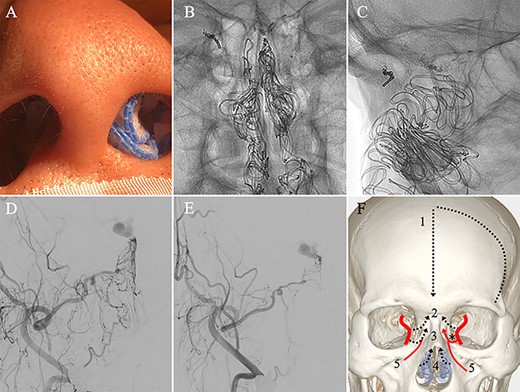

(A) Inserting gauze infiltrated with epinephrine into bilateral nasal cavities. (B and C) Radiograph showing the gauze inserted toward the upper nasal cavity. (D) DSA before inserting the gauze, anteroposterior view, showing blood flow from the right distal IMA. (E) DSA immediately after inserting the surgical gauze, anteroposterior view, showing decreased blood flow from the IMA. (F) Schematic drawing of remaining (red solid line) and occluded feeding arteries (black dotted line) after inserting the surgical gauze. Schema describing that the left dorsal nasal artery (asterisk) remained patent after embolizing the left middle meningeal artery (1), bilateral ethmoid arteries (2) and the right dorsal nasal artery (3), and blood flow from bilateral distal IMAs (4) decreased using our transnasal flow reduction method. (5) Angular artery.